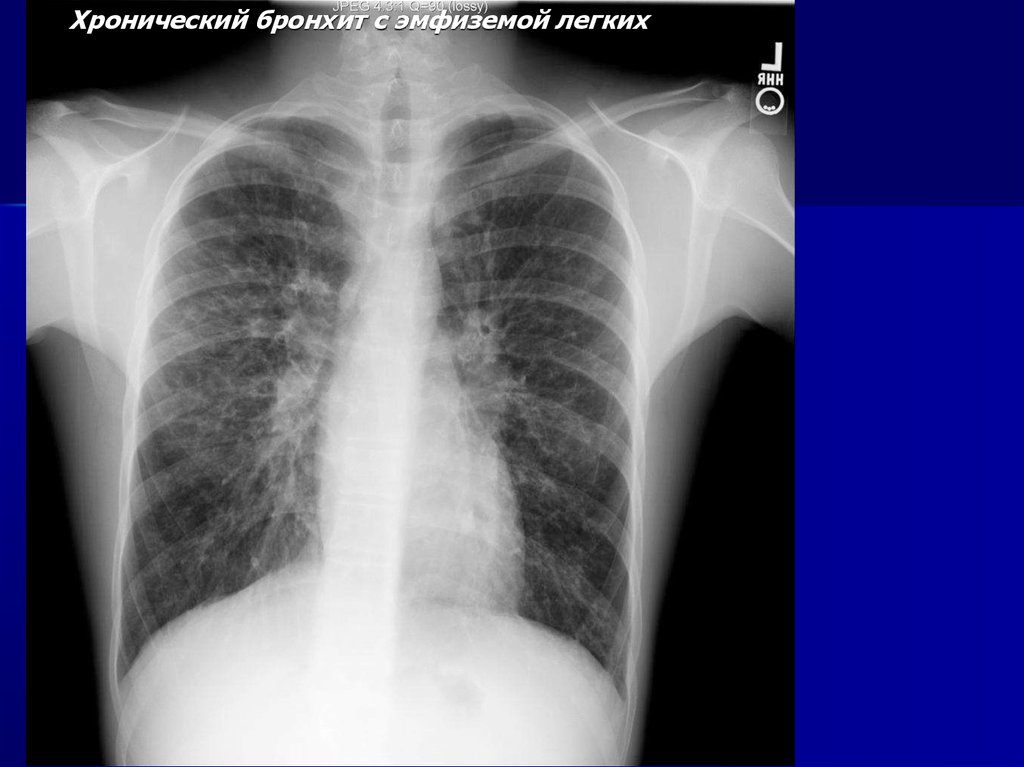

23.

Хронический бронхит с эмфиземой легких